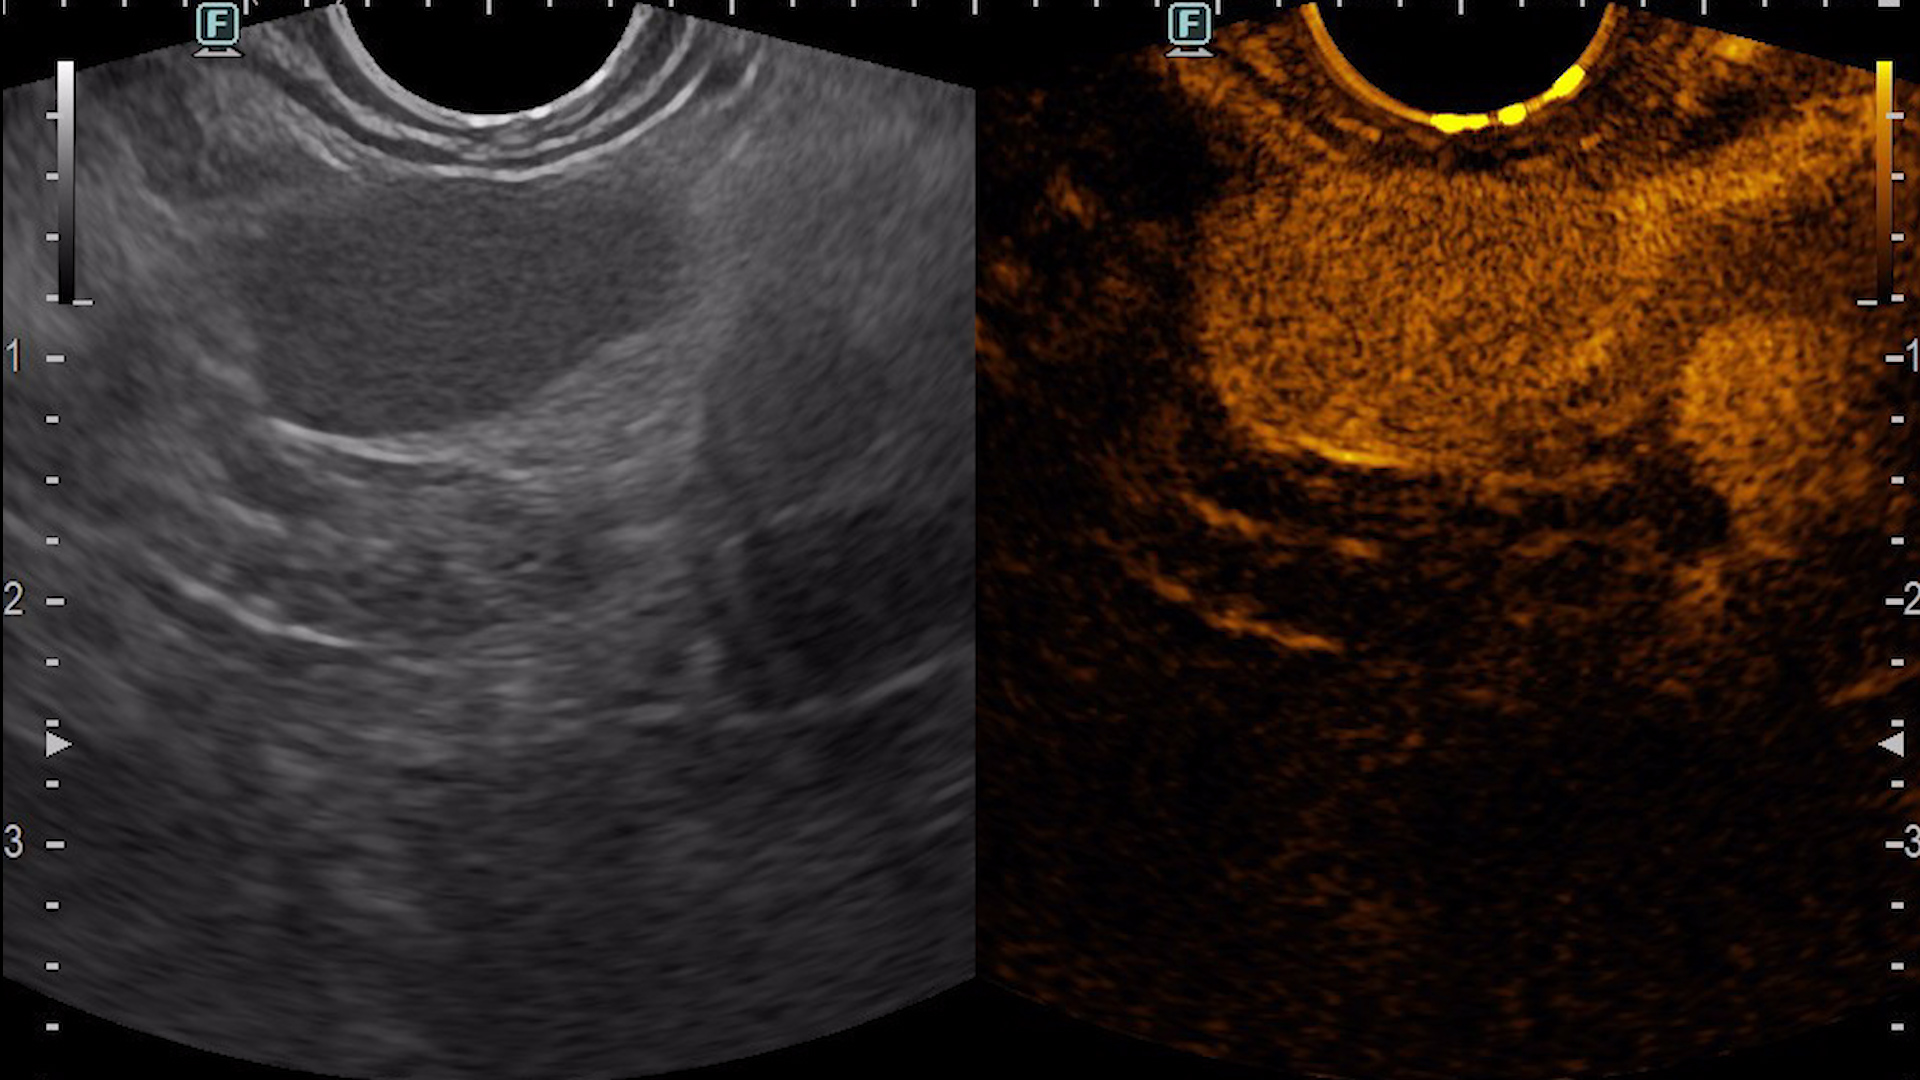

Consequently, an endoscopic ultrasound examination was carried out with tissue acquisition from the mass using a 22G Franssen-type needle (Acquire, Boston Scientific). The tumor was hypervascular on both color Doppler (Fig. 3a), detective flow imaging (Fig. 3b) and contrast-enhanced harmonic imaging (CHI) endoscopic ultrasound (Fig. 4). Histopathology was conclusive for a well-differentiated G1 neuroendocrine tumor, while immunohistochemistry confirmed the diagnosis, showing a Ki 67 index of 1%.